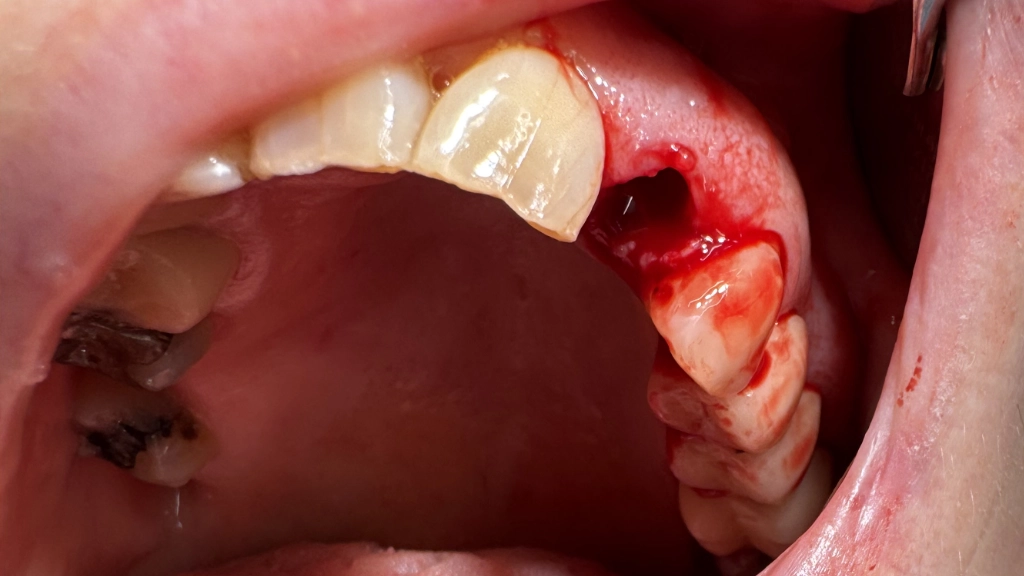

De tandarts verdooft je tandvlees en haalt heel voorzichtig de oude wortel weg. Normaal gesproken zonder boren of snijden. De wond wordt goed schoongemaakt. Het wondje oogt een beetje als een neusgat met een neusbloeding. Al heel snel klontert het weer samen.